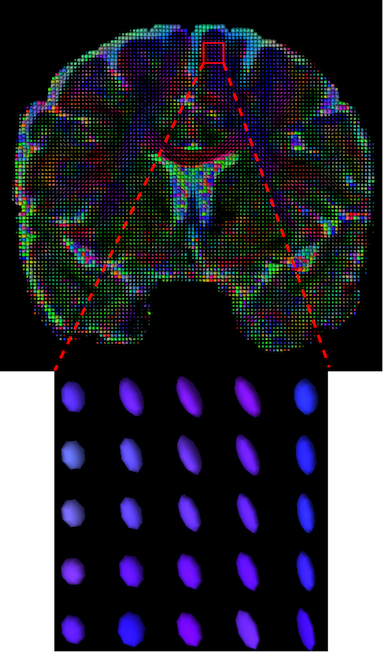

The visualization of inpainted results (showing the whole diffusion tensor for each voxel) generated from different models are demonstrated in Figure 3, where the tensor is represented in RGB coding that colours red, green and blue represent diffusion in the x, y, and z axes respectively. One typical example of reconstruction in the disrupted ROIs has been zoomed for visualization. Compared to the ground truth, TW-BAG is able to generate more distinct orientations following the original distribution and intensity across sagittal, coronal and axial views, which could demonstrate water diffusivity (denoted by eigenvalues of tensor model) more accurately. As indicated in Figure 4, the boundaries and textures of the FA map for TW-BAG are less blurry than the other competing models, validating the effectiveness of TW-BAG from a neuroscience perspective.